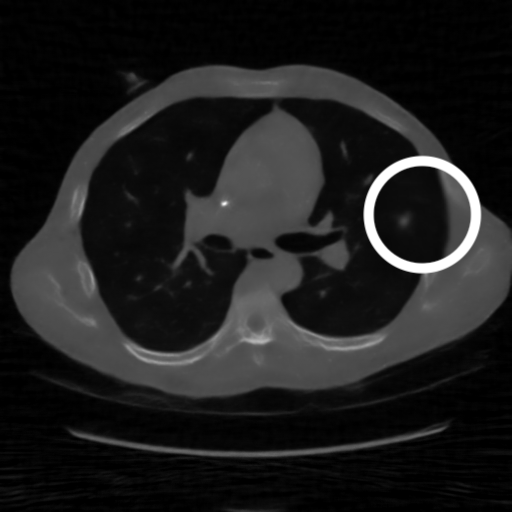

3.1.3 Example 2: data driven reconstruction methods in lung CT screening

In on-going research on photon counting detector types and screening procedures for lung cancer (EPSCR grant: EP/W004445/1) an experiment was conducted testing enhanced reconstruction algorithms. Simulations using less than 10% of a clinical X-ray dose were performed to investigate if data-driven methods could sufficiently enhance the images to clearly see the tumours in the lungs while providing very low amount of dosage to the patients. The corresponding data was a CT-dose simulation, using images from the open LIDC-IDRI dataset (citep \@BBN(Armato et al., 2011)) as references, as well as simulated and reconstructed images with in-house software. Figure 3 shows the results of the experiment. We show the reference image used as basis for the simulation, together with five different reconstruction algorithms. The first is an iterative solver, a gradient descend algorithm with TV minimization (citep \@BBN(Sidky et al., 2012)) and (c)-(f) correspond to machine learning methods: FBPConvnet is a denoising algorithm that cleans the bad image (citep \@BBN(Jin et al., 2017)), LPD is an iterative unrolled method that combines traditional solvers with machine learning (citep \@BBN(Adler and Öktem, 2018)), Noise2Inverse is a self-supervised learning method (i.e. does not require ground truth data) (citep \@BBN(Hendriksen et al., 2020)) and ItNet is another iterative unrolled method, the best performing winner of the AAPM DL-Sparse-View CT challenge (citep \@BBN(Genzel, Macdonald, and März, 2021)). ItNet is also judged here as the best result according to PSNR, SSIM and LPIPS.

Refer to caption

(a) Reference

(b) (27.6, 0.70, 0.37)

(c) (31.9, 0.73, 0.29)

(d) (32.5, 0.84, 0.19)

(e) (32.5,0.77, 0.20)

(f) (33.0, 0.89, 0.12)

Figure 3: Reference image (a) and outputs of different reconstruction methods (b)-(f) applied to dose simulated data. PSNR/SSIM/LPIPS are unable to identify the best reconstruction (c), where also the tumour is visualized well.

FR-IQA mismatches

This experiment was performed to evaluate the quality of different kinds of CT reconstruction, and especially the lung tumour detection capabilities thereof. The best result according to the chosen IQA measures is given by ItNet in Figure 3(f), which performs visually poorly. Not only the tumour (zoomed in white circle) is significantly less visible in the reconstruction, but ItNet also produces structures in the lung that are different than the ones in the reference image; it blurs and lengthens much of the soft tissue present in the lungs and it also created structure from noise in some places. Moreover, the image is overly smooth. Comparing the other reconstruction algorithms, it seems that FBPConvnet Figure 3(c) is the one performing best at preserving the shape of the lung nodule, even when the resulting image contains enhanced pixel-level noise.

We can see here that the qualitative findings strongly contradict the numbers provided by the selected measures. The reconstruction of ItNet, Figure 3(f), is outperforming the other reconstructions in regards of the measures, and the qualitative winner FBPConvnet, Figure 3(c), is judged as second worst by the same measures. This experiment suggests that the discussed measures are not a good choice for that kind of CT reconstruction applications and are yielding misleading results.